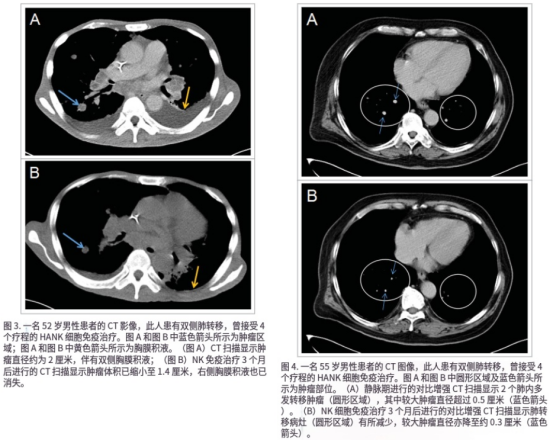

针对加强型NK细胞,目前部分研究机构报告了在晚期实体瘤患者中的探索性应用结果:联合化疗用于肝癌、胰腺癌、结直肠癌等,疾病控制率可达80%左右;对于血液肿瘤,临床应答率超过70%。